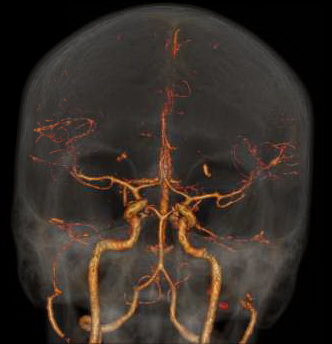

CTA of the Head and Neck image A for Radiology

How it works: CT angiography (CTA) evaluates the major vessels of the head, neck or both. An iodine based contrast agent is rapidly injected through an IV placed in a vein, usually in the arm. A CT scan uses x-rays to acquired images as the contrast bolus passes through the arteries. The data can then be reviewed in multiple planes, and 3 dimensional images can also be created for review.

Equipment: Most commonly, a 64 channel Philips CT scanner is used, however, in some situations a 16 or 256 channel CT scanner may be used. OHSU is an ACR accredited CT facility.

Benefits: CT angiography is a fast and minimally invasive method of evaluating vessels for abnormalities such as narrowing, blockage, aneurysms, and other vascular malformations.